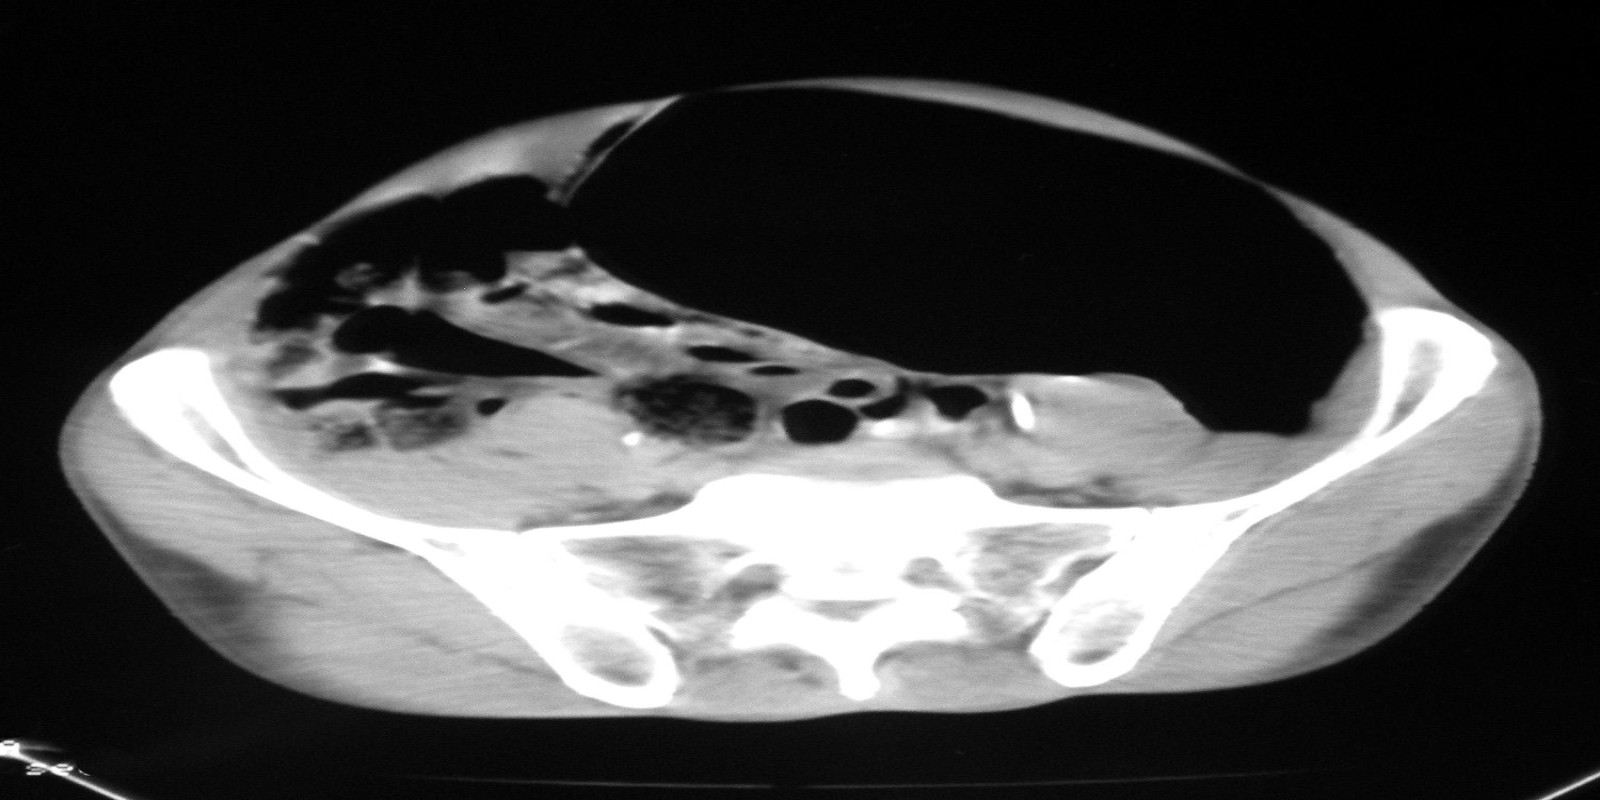

Eventração diafragmática

Diaphragmatic Eventration